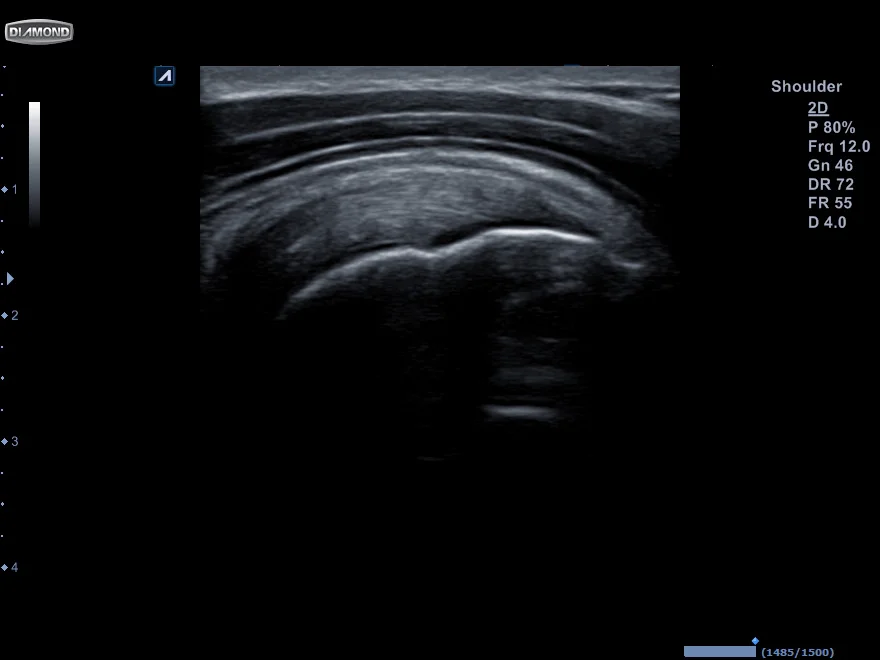

Diagnostisk ultralyd

DUS (Diagnostic Ultra Sound) har vært brukt i mange år, men det er først de senere år det har blitt "vanlig" i fysikalske klinikker. Dette er dels fordi kurs og utdanning har blitt lettere tilgjengelig og mye fordi apparatene har blitt billigere og bedre. Fordelen med ultralyd er at man får smale snitt av vevet med høy oppløsning. Det er derfor lettere å se rupturer, kalk og veske som man ellers kunne gått glipp av på MR. På sener kan man trygt si at det er bedre enn MR. Men en metode er dessverre ikke bedre enn klinikeren som utøver den. Derfor er den største feilkilden innen DUS personen som tolker bildene.

DUS er ikke ment som et verktøy som man bruker alene. Det er alltid grunnet i klinisk undersøkelse og grundig anamnese. Dersom man undersøker et segment bør man på forhånd ha gjort seg en formening om hva man kommer til å finne. Klinikken er fundamentet og DUS bekrefter eller avkrefter det man mistenker på bakgrunn av klinisk testing.